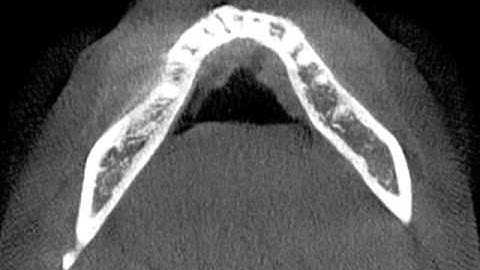

Fusion of Photogrammetry and 3D CT Scanning (3D Computed Tomography)